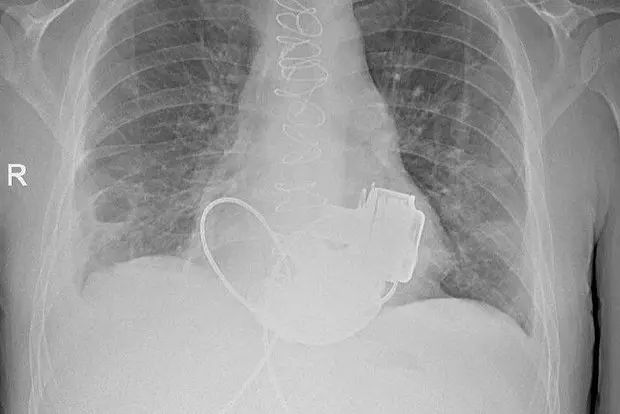

Команда Мариинской больницы под руководством Игоря Реутского, проявив высочайшую компетентность и решительность, приняла инновационное решение: вместо установки одного искусственного желудочка, как делалось ранее, было решено имплантировать одновременно оба. Это непростое вмешательство длилось около четырёх часов, и основной сложностью стала необходимость идеальной синхронизации работы двух искусственных механизмов.

После сложнейшей операции пациенту пришлось пережить нелёгкий период реабилитации. Персонал клиники разработал для него индивидуальную программу адаптации к жизни с новыми устройствами, а сам мужчина проявил удивительную силу духа, освоив все тонкости современного протезирования сердца. Теперь, спустя несколько месяцев регулярного наблюдения и восстановления, его состояние оценивается как стабильное, а специалисты готовят его к выписке домой.